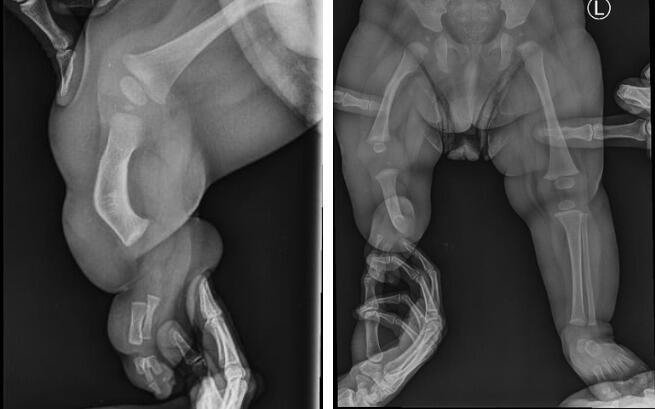

23 marca odbyliśmy konsultację z doktorem Paleyem w Paley European Institute w Warszawie. Podczas wizyty potwierdził, że wada Leosia jest bardzo trudnym i rzadkim przypadkiem, co wynika z połączenia dwóch poważnych schorzeń: hemimelii strzałkowej (czyli braku kości strzałkowej, skrócenie kończyny, deformacja stopy) oraz wrodzonego niedorozwoju kości udowej.

Zazwyczaj dzieci zmagają się tylko z jednym z nich, natomiast u Leona występują oba jednocześnie, co sprawia, że leczenie będzie długie i wieloetapowe. Bez operacji różnica w długości nóżek będzie się z czasem pogłębiać i w dorosłym życiu może sięgnąć nawet około 30 cm (!), co znacząco wpłynęłoby na jego sprawność i codzienne funkcjonowanie.

Podczas wizyty wykonano nowe zdjęcia RTG. Na ten moment różnica długości nóżek wynosi już 9,5 cm… To pokazuje, jak dynamicznie postępuje wada i jak pilnie Leon potrzebuje specjalistycznego leczenia.

Leoś urodził się ze znacznie krótszą prawą nóżką. Lekarze przewidują, że różnica długości może osiągnąć nawet 30 centymetrów. Skrócona kość udowa, skrócona kość piszczelowa, brak kości strzałkowej, zdeformowana stopa z trzema złączonymi paluszkami… Diagnoza: hemimelia strzałkowa – wada, która zabiera beztroskie dzieciństwo i odbiera szansę na normalny krok.